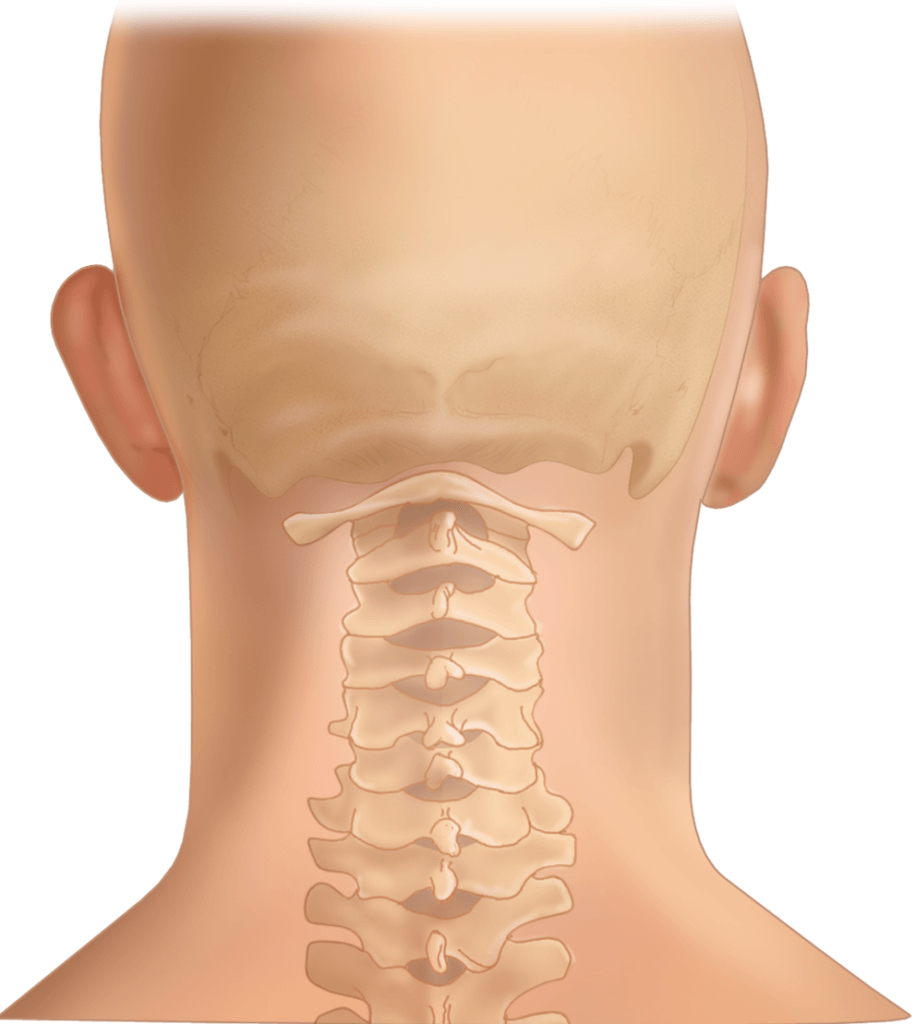

The Cervical Spine: Anatomy, Function, and Common | Spine Center of …

Normal Cervical Spine Anatomy – TrialExhibits Inc.

Anatomy of the Cervical Spine – TrialExhibits Inc.

The Cervical Spine – Features – Joints – Ligaments – TeachMeAnatomy